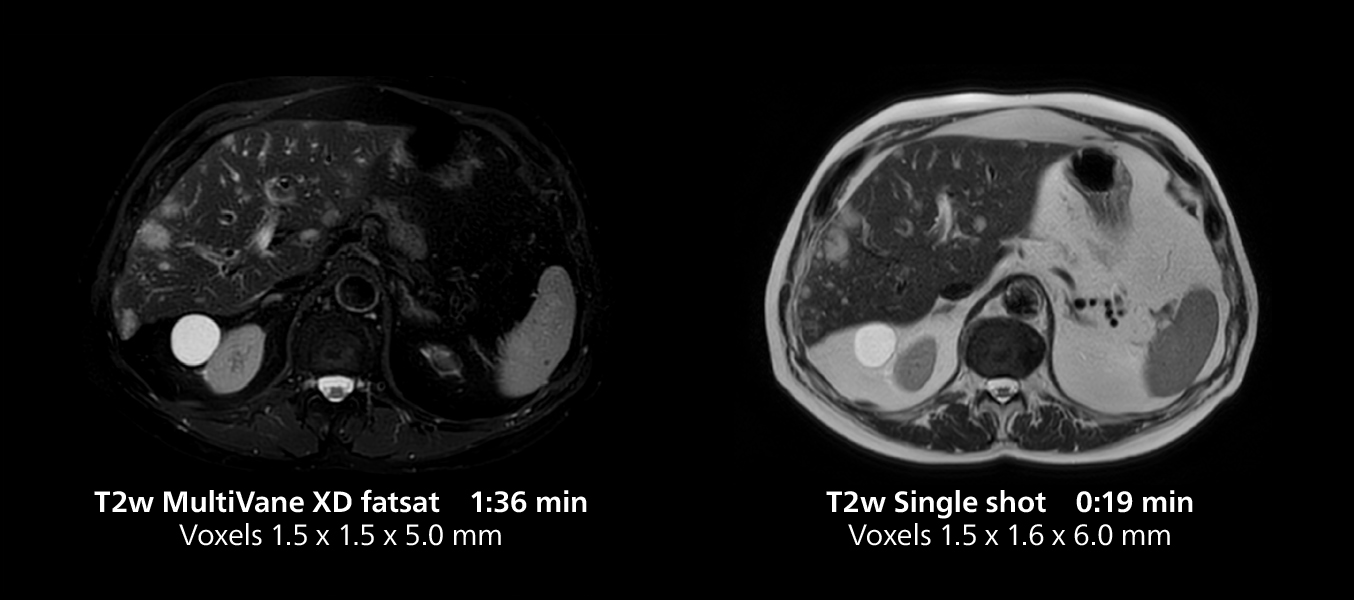

Liver imaging using MR 5300

This case includes 3D free breathing and 4D dynamic free breathing MRI of a metastasized liver. A high quality fatsat sequence with good resolution is obtained in 1:36 minutes with T2-weighted MultiVane XD.

Free-breathing scans provide reproducibility and patient comfort

Dr. Gellée highlights the robust free-breathing scans as “the feature that makes the biggest difference in my daily work. The 3D free breathing sequences are very reproducible, and the axial acquisition is very good. For example, in endometriosis, which is one of my focus areas, it provides high contrast and good resolution so that I can see small details. We also use free breathing for liver and pancreas imaging. In multi-phase liver studies, 4D Free Breathing delivers 3-second temporal resolution, making a dynamic scan with more than one arterial phase possible.”

She also uses free breathing with 3D mDIXON to obtain in-phase, water and fat images in a single scan. “It is very reproducible before and after gadolinium, which makes it useful for liver imaging,” she adds.